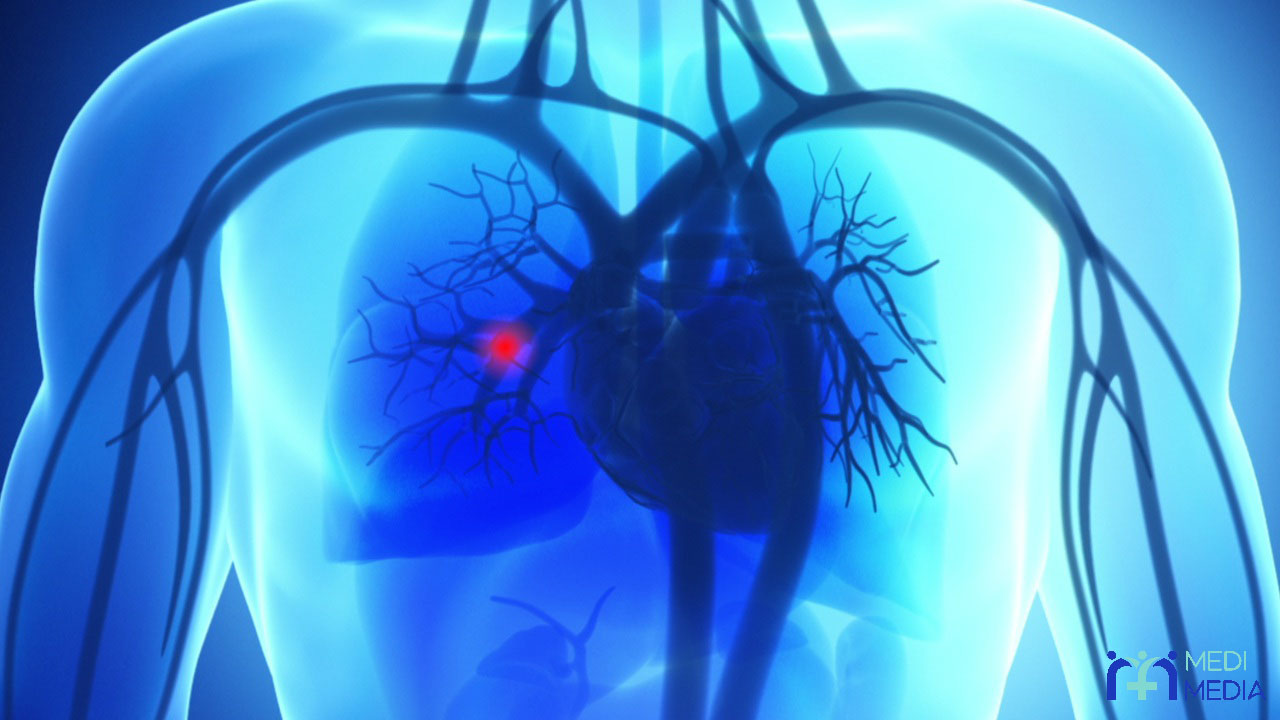

آمبولی ریوی بیماری است که در طی آن، در عروق خونی قسمتی از بدن جسمی مسدود کننده مثلاً لخته ی خون ایجاد می شود و سپس آن لخته در عروق و همراه با جریان خون حرکت می کند و خودش را به شریان های خون رسان به ریه ها می رساند و در آن جا باعث ایجاد انسداد در مسیر جریان خون می شود.

به طور معمول علت اصلی آمبولی ریوی ایجاد لخته ی خون در قسمتی از بدن و حرکت و رسیدن آن لخته به عروق خون رسان به ریه ها و ایجاد انسداد در این عروق می باشد و کمتر پیش می آید که این انسداد به خاطر تجمع قطرات چربی، حباب هوا، بخشی از یک تومور یا ذرات دیگری که وارد خون می شوند، باشد و اغلب آن جسم مسدود کننده، لخته ی خون است.

لازم به ذکر است که این لخته اغلب در ساق پاها یا بازوها ایجاد می شود و سپس از این نواحی همراه با جریان خون به سمت شریان های ریوی حرکت میکند. توجه به این نکته نیز ضروری است که این انسداد به هر دلیلی که باشد، چه ایجاد لخته ی خون چه تجمع قطرات چربی و… باعث کاهش خون رسانی و در پی آن کاهش اکسیژن رسانی به بافت ریه ها می شود.